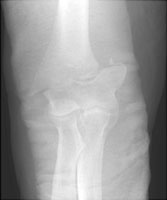

- Click on the image for a larger versionBAP radiograph of the elbow. The patient has sustained an obliquely oriented supracondylar fracture and has been placed in a cast.